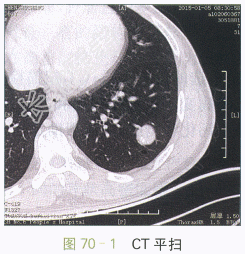

影像学资料如图70-1~图70-4所示。

图70-1~图70-4胸部CT平扫与增强:左肺下叶类圆形肿块,边缘光滑,瘤灶内斑点状钙化,呈爆米花样改变,增强扫描未见明显强化

读片分析:CT表现:左肺下叶类圆形肿块,直径约2.7cm,边缘光滑清楚,瘤灶内见多发的小斑片状钙化,呈爆米花样改变,增强扫描未见明显强化。